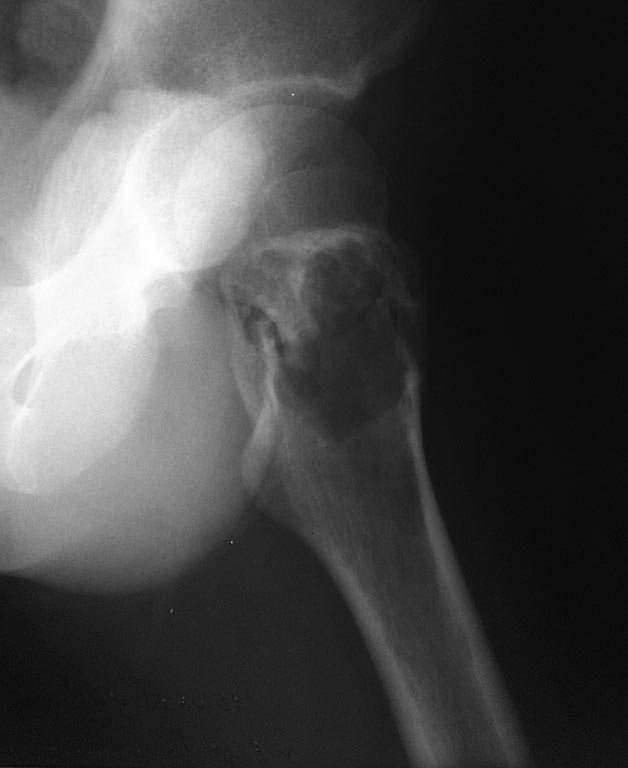

Уважаемые коллеги. Помогите определиться с тактикой лечения. Пациент 1993г.р (20 лет), поступил жалобами :на боли в области левого тазобедренного сустава, нарушение опорной функции левой нижней конечности.Anamnesis morbi: Со слов пациента и медицинской документации 15.08.2013г упал на область левого тазобедренного сустава. По скорой помощи госпитализирован в одну из клиник Астаны, где произведена рентгенография левого тазобедренного сустава, на которой выявлено образование проксимального отдела левой бедренной кости. Для выбора тактики дальнейшего лечение пациента, консультирован остеоонкологом, рекомендовано оперативное лечение в плановом порядке в условиях профильного отделения остеоонкологии АО «РНЦ НМП».Об-но: по внутренним органам без особенностей.Status localis: При осмотре пациент на кровати лежа на спине. Левая нижняя конечность без иммобилизации, ротирована наружу, в области левого тазобедренного сустава отмечается незначительный отек. Осевая нагрузка на левую нижнюю конечность болезненна. При пальпации отмечается резкая боль в области левого тазобедренного сустава. Симптом «прилипшей пятки» отрицательный с обеих сторон. Относительная длина обеих нижних конечностей одинаковая. На периферии конечностей нейроциркуляторных нарушений нет. На представленной R-грамме левого тазобедренного сустава–выявляется деструктивная полость в вертельной области левой бедренной кости нарушение костной структуры с образованием костной полости с тонкостенными перегородками.Границы полости крупно ячеистые. Госпитализирован с предварительным диагнозом: Остеобластокластома вертельной области левой бедренной кости. Закрытый патологический чрезвертельный перелом левой бедренной кости? 04.09.13г 1-м этапом произведена: Операционная биопсия из проксимального отдела левой бедренной кости. Заключение патолого - гистологического исследования: Патоморфологическая картина может соответствовать костной кисте. Пациенту произведено КТ обеих тазобедренных суставов. Заключение: КТ - признаки объемного образования области шейки и большого вертела левой бедренной кости дифференцировать с фиброзной дисплазией. Сростающийся патологический чрезвертельный перелом левой бедренной кости. ОАК, ОАМ, коагулограмма в пределах нормы.